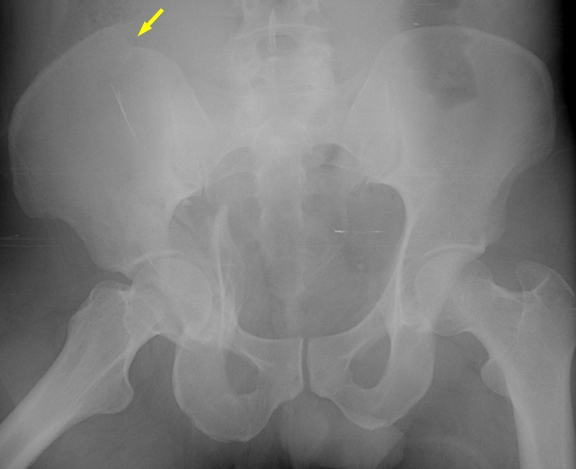

Imaging

• Radiographs

• Recommended views

• AP

• judet

•  obturator oblique

• shows profile of obturator foramen

• shows anterior column and posterior wall

• iliac oblique

• shows profile of involved iliac wing

• shows posterior column and anterior wall

• Findings

• radiographic landmarks of the acetabulum

• iliopectineal line (anterior column)

• ilioischial line (posterior column)

• anterior wall

• posterior wall

• teardrop

• weight bearing roof